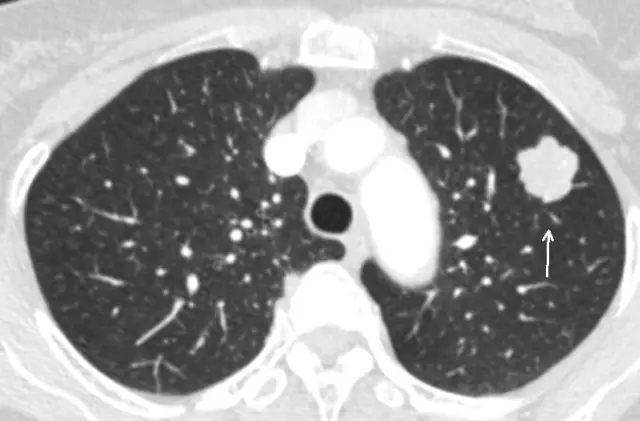

是指肺內直徑≤3cm的密度增高影,通俗講就是CT上黑色的肺里有小白點。>3cm的白色塊狀影稱為肺腫塊,通常腫瘤的可能性很大。

結節直徑≤3cm

結節直徑>3cm